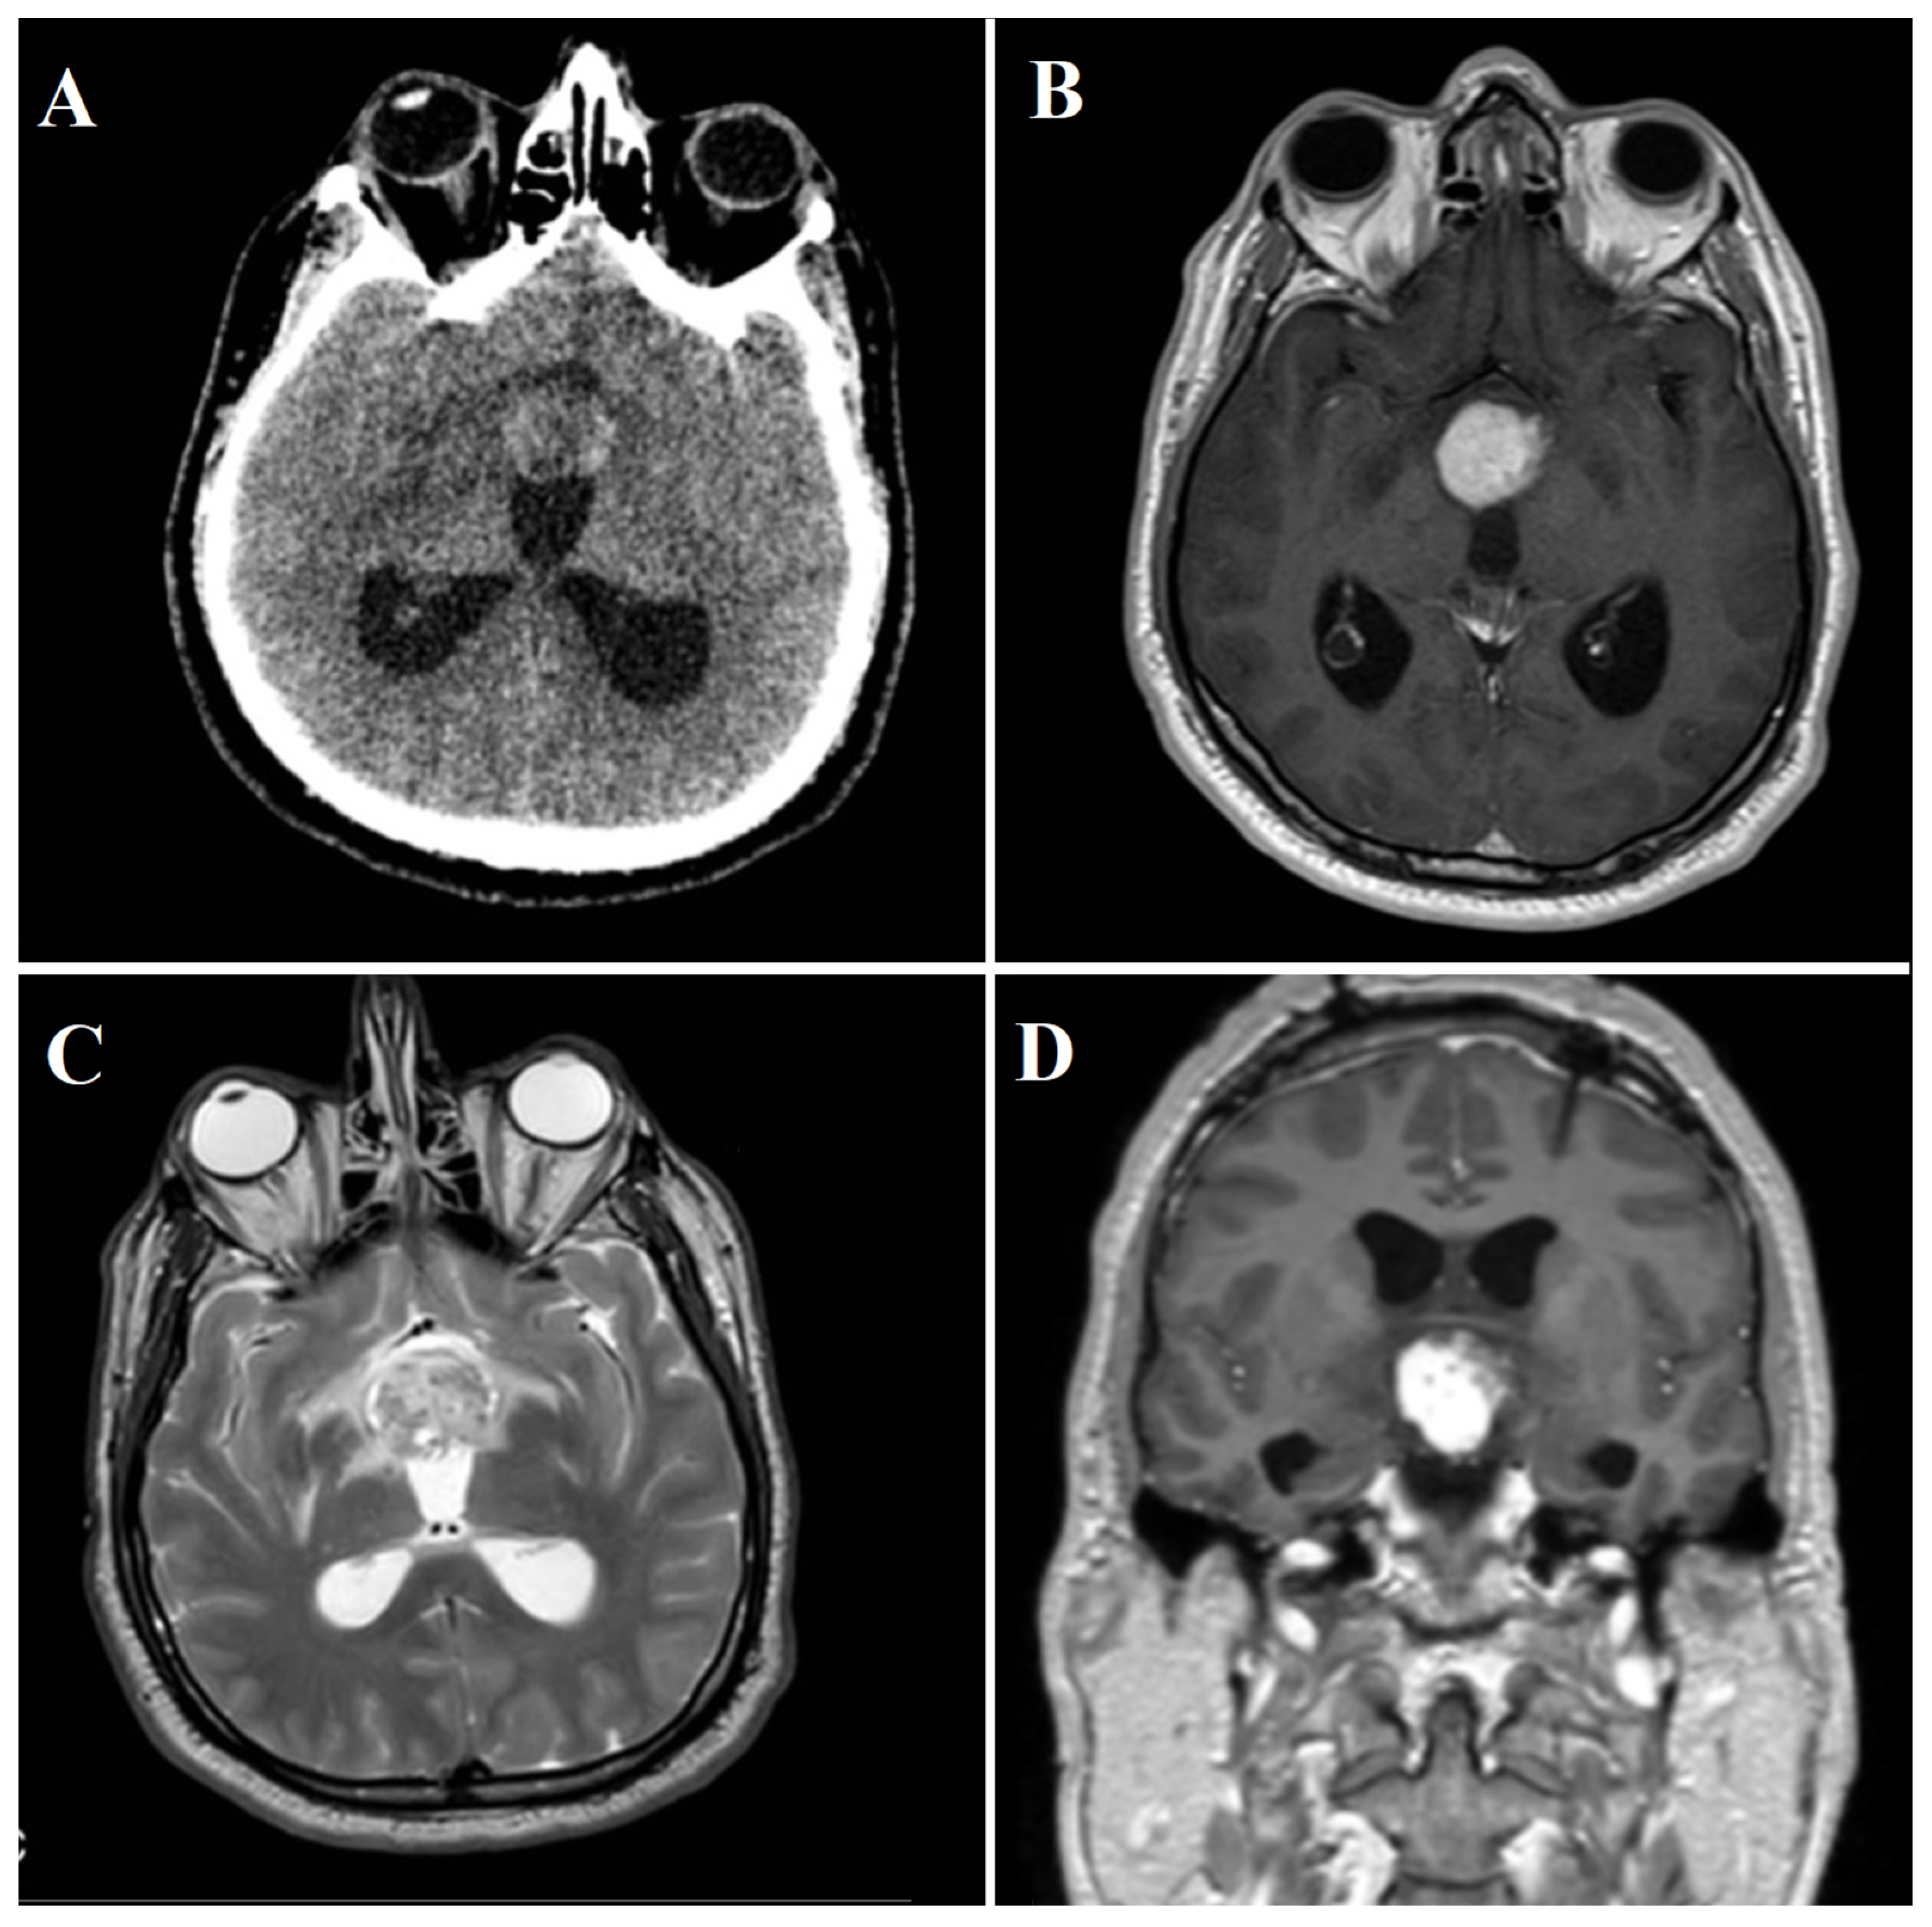

A 48-year-old male presented at the Emergency Department in April 2022, with an acute stuporous state and no history of neurologic disease or notable trauma. Physical examination revealed a third cranial nerve palsy on the right side. A brain computed tomography (CT) scan showed a hypothalamic lesion causing obstructive hydrocephalus (Figure 6A). CT angiogram showed no evidence of vascular abnormalities. The patient was promptly referred to the Neurosurgical Department and underwent urgent bilateral external ventricular drainage placement to firstly treat acute hydrocephalus.

Figure 6.

(A) Initial brain CT-scan showing a heterogeneous spontaneous hyperdense hypothalamic lesion with associated hydrocephalus. (B) Axial MRI appearance of the lesion, with intense gadolinium enhancement. (C) Inhomogeneous hyper-intensity on MRI T2-weighted images. (D) Coronal MRI appearance of the lesion, with intense gadolinium enhancement.

3.2.2. Radiological Findings

Once the patient was clinically and neurologically stable, a brain MRI was performed, revealing an expansive hypothalamic lesion infiltrating the anterior part of the third ventricle. T2-weighted images (T2WI) displayed inhomogeneous hyper-intensity, while T1-weighted images (T1WI) indicated low signal intensity. In addition to an altered signal in the optic chiasm and tracts, the lesion appeared close to the pituitary stalk. Susceptibility weighted imaging (SWI) sequences detected intralesional bleeding and microcalcification. Post-contrast administration revealed intense enhancement (Figure 6B–D), accompanied by increased perfusion indexes.